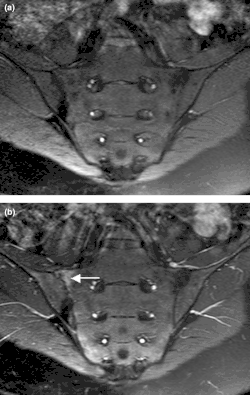

Además, como prueba de imagen es frecuente realizar una resonancia magnética nuclear local y, en ocasiones, una prueba radiográfica.[9]